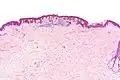

Low magnification

Micrograph of a dysplastic nevus showing the characteristic rete ridge bridging, shouldering, and lamellar fibrosis. H&E stain.